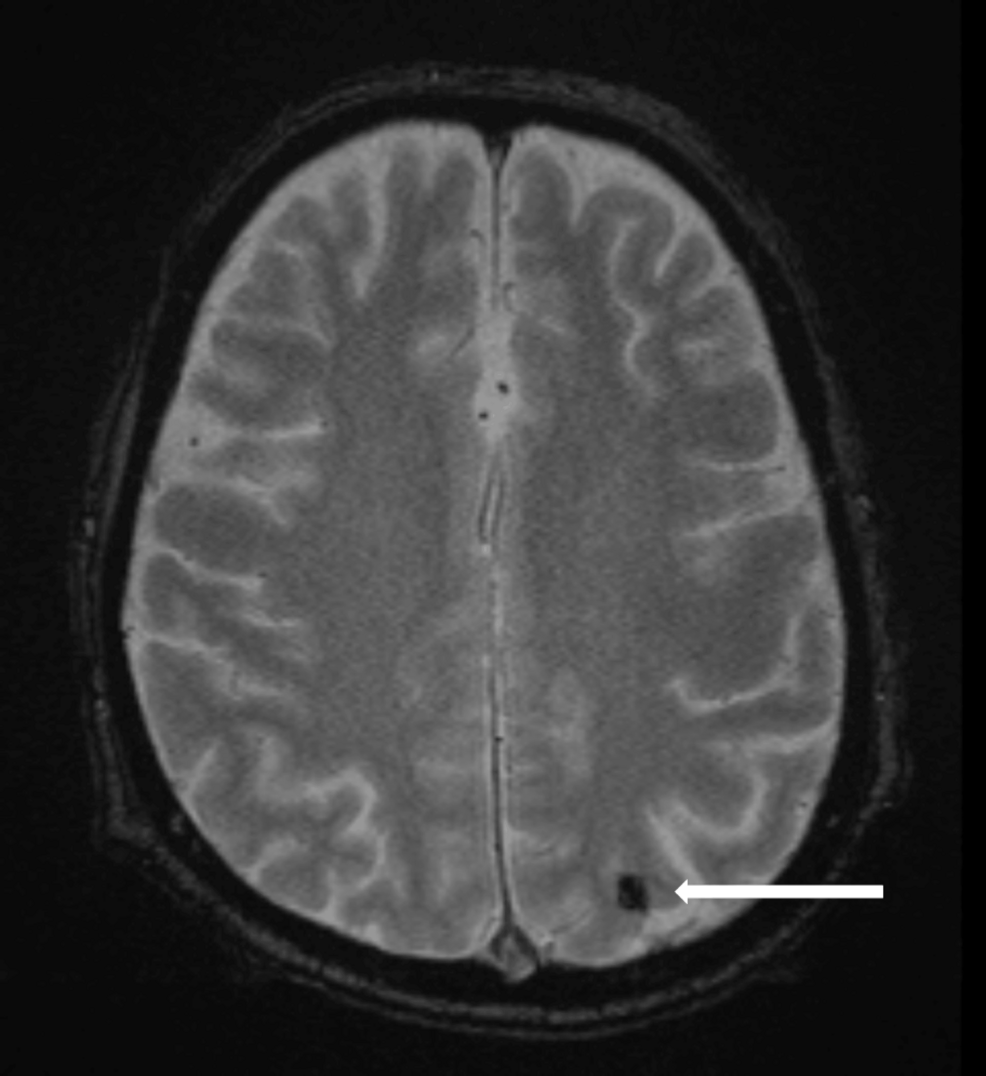

Introduction to the Complexities of IE and Stroke

Infective endocarditis (IE), a life-threatening infection of the heart’s inner lining or valves, can led to devastating neurological complications. Cerebral embolism, a common manifestation of IE, occurs when infected vegetations break loose and travel to the brain, causing stroke. This can lead to severe disability and even death. Furthermore,these emboli can result in subarachnoid hemorrhage (SAH),further complicating the clinical picture. This case report highlights the challenges and potential benefits of rescue thrombectomy in such a complex scenario.

Associated Risks: The friable nature of the vegetations increases the risk of hemorrhagic transformation and subarachnoid hemorrhage (SAH).

Early Recognition: Early detection through prompt imaging (CT, MRI) is essential for guiding treatment strategies.

Subarachnoid Hemorrhage and its Implications

Mechanism: Cerebral emboli can lead to weakened blood vessels and subsequent SAH.

Neurological Impact: the presence of SAH can significantly worsen patient outcomes.